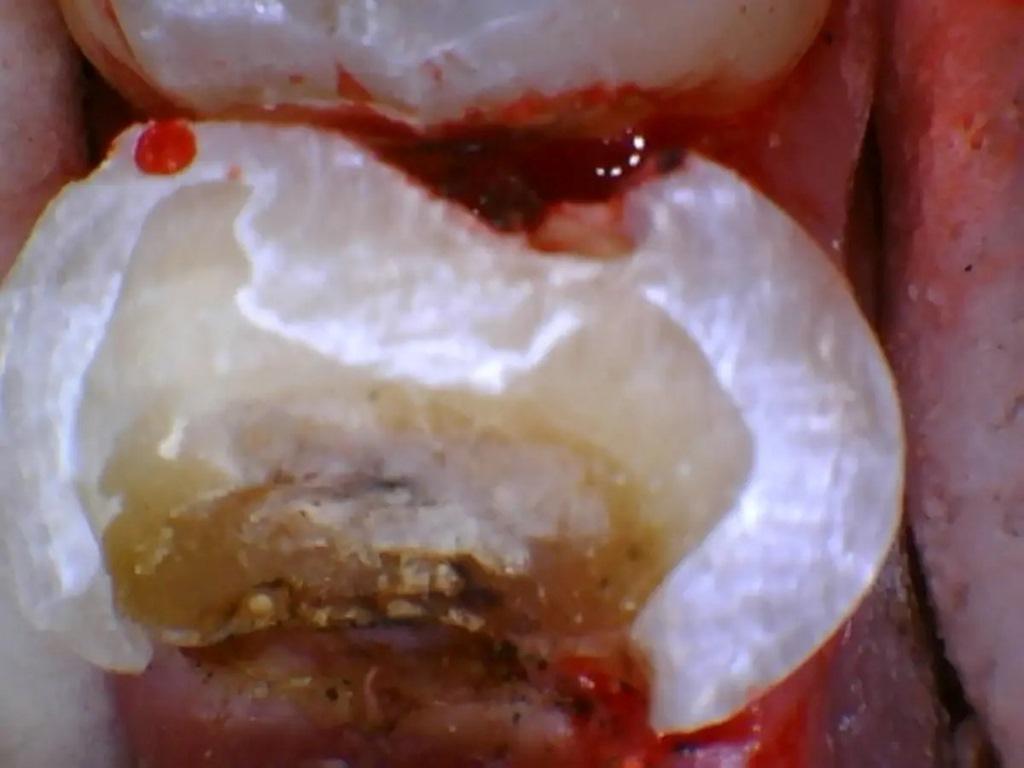

В буккальном преддверии ввели местный анестетик. Кариес и пораженная структура зуба были удалены с помощью твердосплавных и алмазных боров. Было отмечено очень небольшое обнажение пульпы (фото 14). После обсуждения с пациенткой вариантов немедленного эндодонтического лечения или лазерной обработки обнажения и установка вкладки с последующей установкой коронки (при условии, что в течение следующих нескольких недель не возникнет никаких симптомов), пациентка выбрала лазерное лечение пульпы. Nd:YAG-лазером в режиме абляции была проведена лазерная обработка поверхности пульпы после удаления кариеса при 50-75 Дж (фото 15). Затем в тех же настройках использовали лазер мощностью до 162 Дж для стерилизации окружающих структур зуба и биостимуляции, как описано в двух предыдущих клинических случаях. С лингвальной стороны в дентин был введен стабилизирующий штифт, чтобы помочь стабилизировать образование вкладки. Для покрытия нижележащей пульпы было нанесено небольшое количество стеклоиономерного цемента GC FujiCEM. Затем на окружающую здоровую структуру зуба был нанесен самоадгезивный композитный цемент RelyX Unicem (3M ESPE), чтобы обеспечить хорошее сцепление материала культи с дентином (фото 16). Подготовка коронки была завершена. Был сделан слепок, изготовлена временная коронка и зацементирована с помощью цинкоксидэвгенольного цемента IRM (Dentsply Sirona). Пациентка вернулась для послеоперационного осмотра зуба через неделю и сообщила об отсутствии какой-либо чувствительности к температуре или окклюзии временной коронки. Слепок был отправлен в лабораторию для изготовления коронки. Затем, через две недели, пациентка вернулась для окончательной установки коронки и по-прежнему отмечала отсутствие чувствительности. Временная коронка была снята, на окончательная коронка была установлена с помощью самоадгезивного композитного цемента RelyX Unicem, проверена и скорректирована окклюзия.

Фото 14: Обнажение пульпы после удаления кариеса.